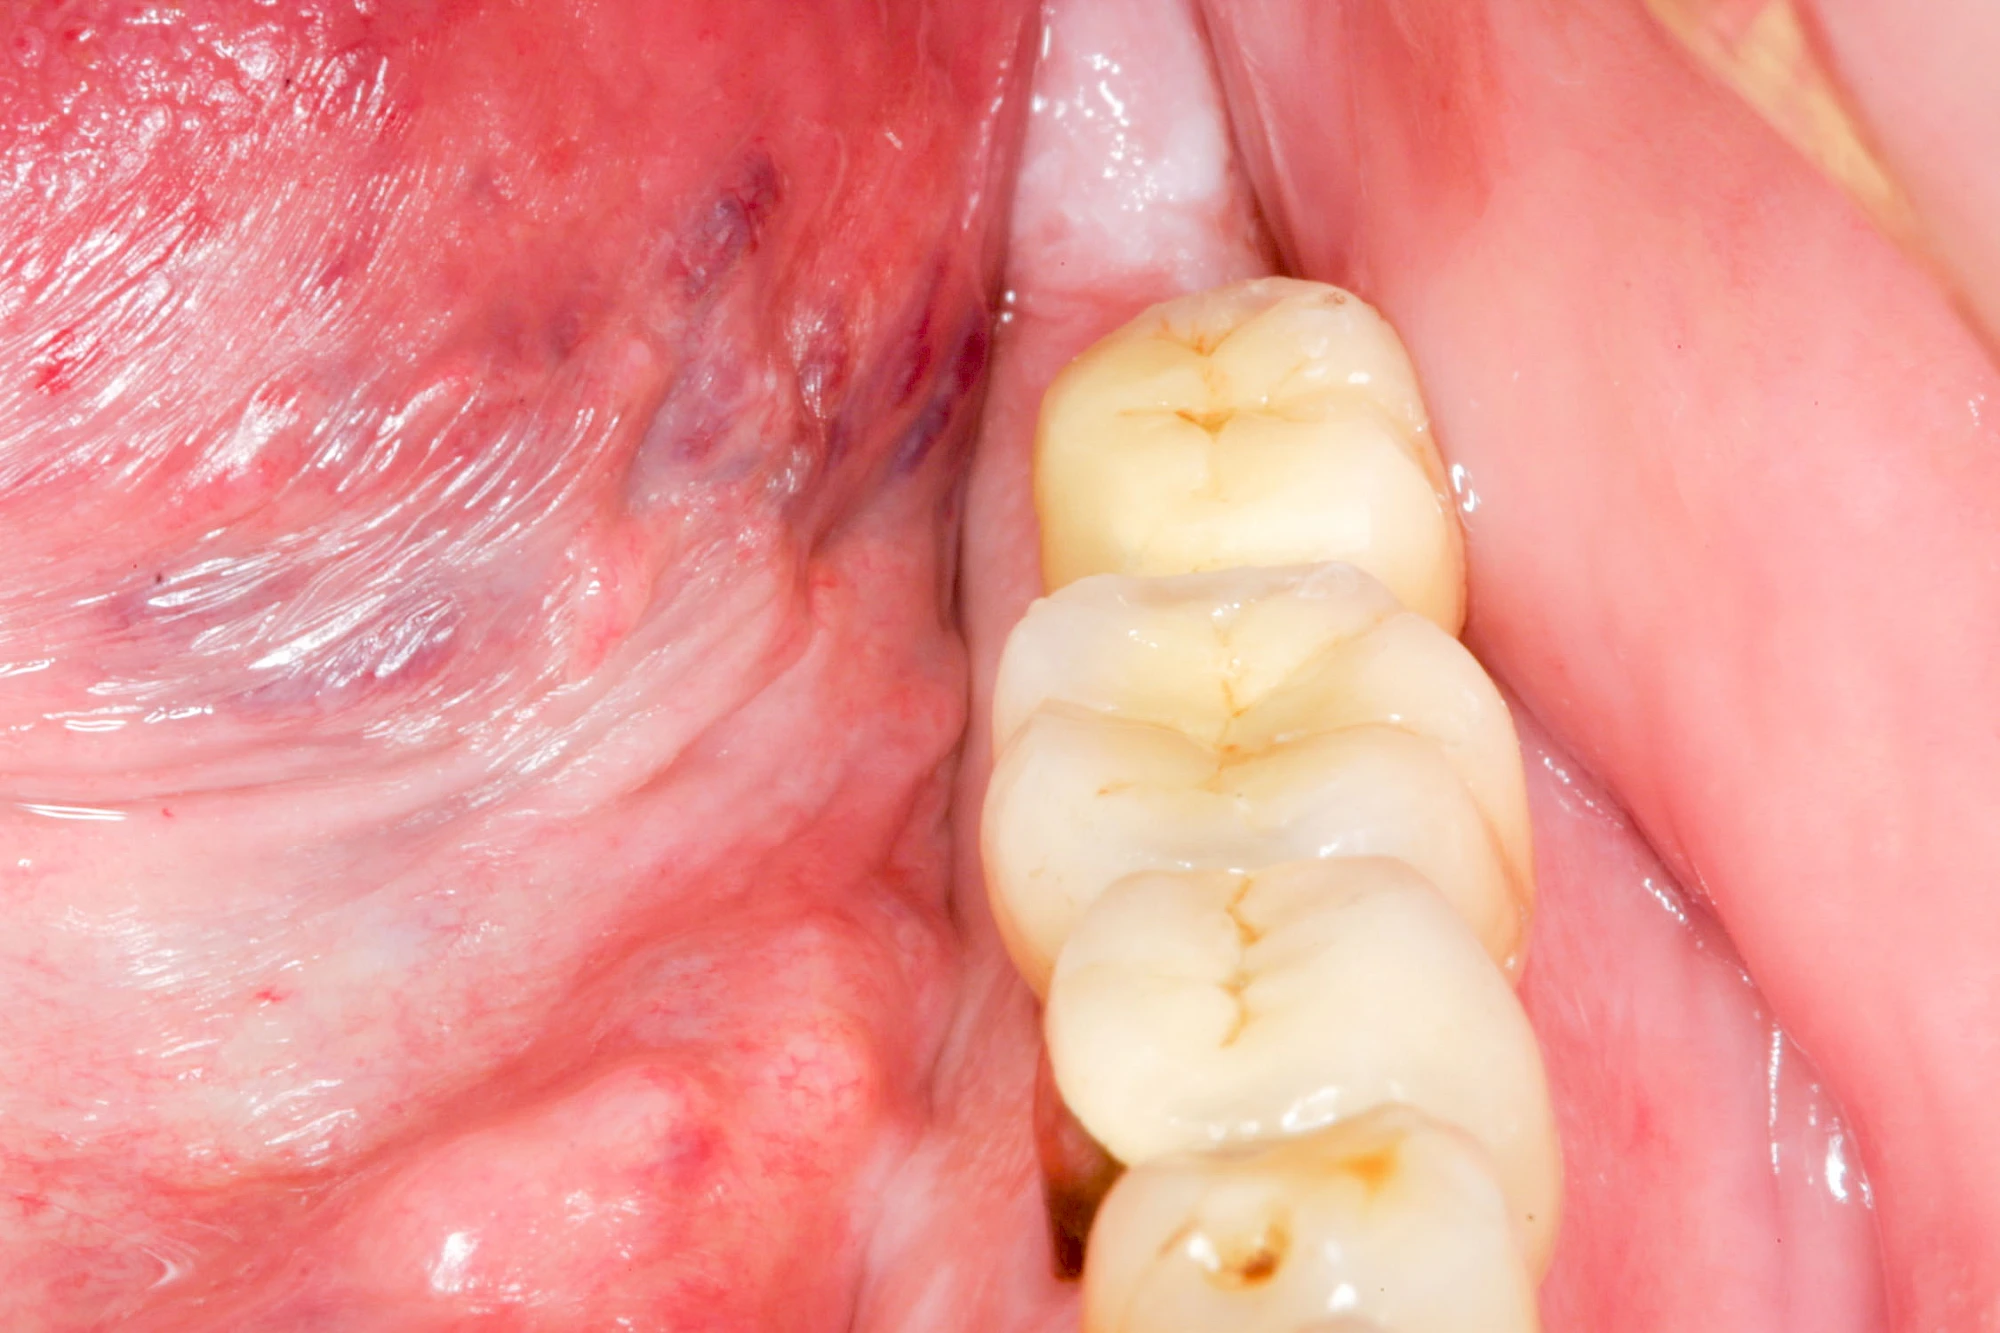

Knochenaufbau und Implantateinsatz

Ist nicht genügend Knochen zur Verankerung eines Implantates vorhanden, kann über einen sogenannten Knochenaufbau die Möglichkeit für das Einbringen eines Implantates geschaffen werden. Dazu kann z. B. Knochen aus der Kieferwinkelregion oder auch aus der Kinnregion entnommen und im Bereich der Fehlstellen aufgetragen werden. Auch künstliches Knochenmaterial kann dabei zum Einsatz kommen.